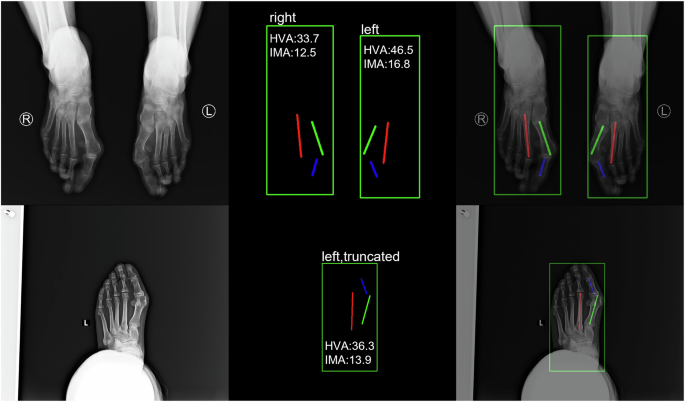

Examples of annotated images of one foot (top) and two feet (bottom). On the left is the de-identified original image; in the middle are the annotated boxes and line segments; and on the right is the fused image with the annotation results. The foot in the top image is labeled as “truncated” due to part of the foot being obstructed by the leg.